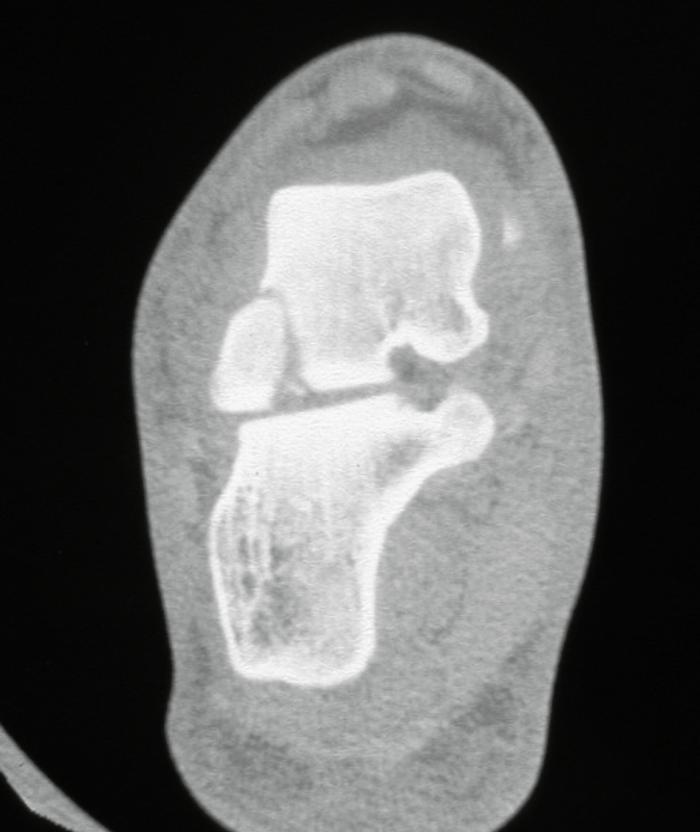

Lateral process of the talus: This is known as the snowboarder’s fracture and is another of the fractures along the lateral border of the foot which may be misdiagnosed as an ankle sprain. It is thought that 40-50% of these fractures can be missed on initial presentation, as the lateral process is very close to the tip of the fibula and the lateral ligaments. The fracture is uncommon, comprising <1% of ankle injuries. The mechanism is thought to be dorsiflexion and inversion of the foot. Careful palpation of the lateral border of the foot will reveal tenderness over the lateral process. The fracture is difficult to diagnose on plain X-rays, because of overlapping bony structures, and an index of suspicion is necessary. A lateral view of the foot, AP mortise view of the ankle and a Broden’s view of the subtalar joint are the best views to show it. Sometimes the degree of pain and swelling may suggest an underlying injury, despite negative X-rays, and a CT is necessary (Figure 5).

Fig 5.jpg

Figure 5: CT showing fracture lateral process talus.

Treatment depends on the size of the fracture, whether it is displaced and whether it involves the joint. Displaced fractures involving the articular surface are best treated with internal fixation. Delayed diagnosis >2 weeks has been associated with poorer outcomes.